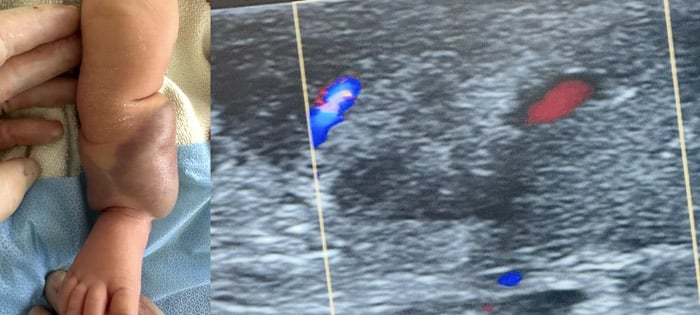

Echo-guided puncture of the common femoral artery

Selective angiography of posterior tibial artery

Perfusion reduction of the tumor by angiography and duplex scan

Normal perfusion of the foot and of posterior tibial artery and vein. Pedal arteries palpable.